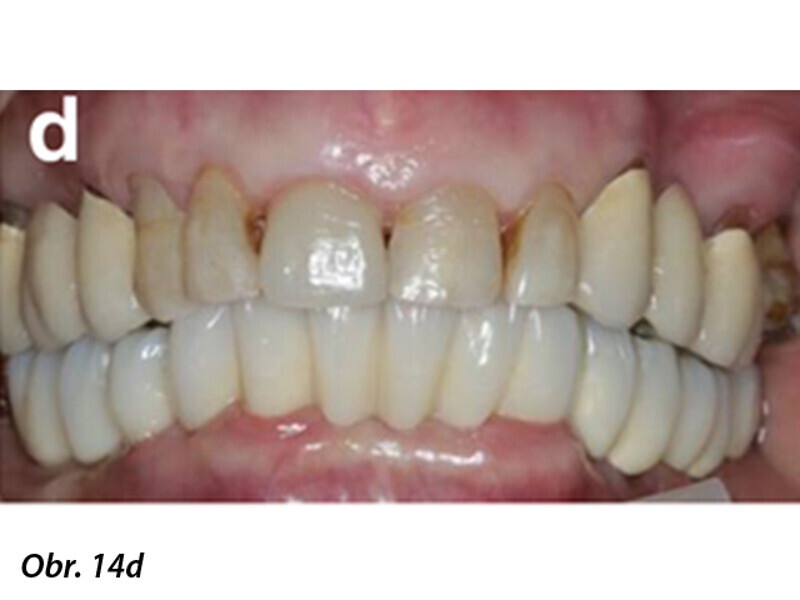

Počítačem asistované, šablonou se řídící okamžité zavedení a zatížení implantátu v dolní čelisti